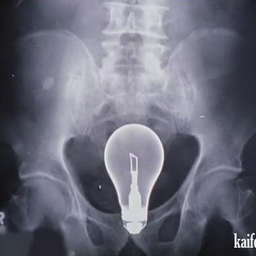

10 признаков того, что ты учишься в медицинском университете.